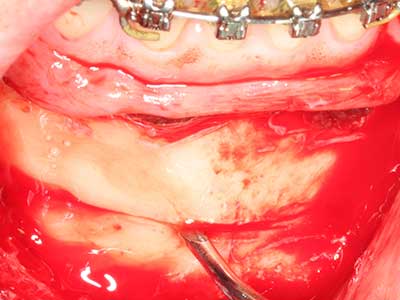

Fig. 1: Preparación de una tapa ósea conforme con Piezomed (W&H, Salzburgo, Austria)

Fig. 2: Defecto del maxilar superior lateral vertical y horizontal con línea de la sonrisa alta, con indicación para la reconstrucción antes del implante.

Fig. 3: La separación basal del bloque se ve facilitada con piezas dotadas de una angulación especial.

Fig. 4: Con la rasqueta ósea se obtienen virutas adicionales de hueso autógeno.

Fig. 5: Comprobación de las dimensiones del bloque en la zona de recepción.

Fig. 6: Después de la preparación de un colgajo mucoperióstico, se prepara el acceso al seno maxilar mediante la técnica piezoeléctrica.

Fig. 7: La preparación inicial de la mucosa del seno maxilar también puede realizarse asistida por ultrasonidos.

Fig. 8: Una vez realizada la elevación del seno, la partición crestal del hueso se fija en la cresta maxilar deficitaria.

Fig. 9: Rebase con material de reemplazo óseo bovino (Cerabone 0,5-1mm, Botiss Bio-materials, Berlín) y hueso autógeno (vista palatinal).

Fig. 10: Cobertura del área aumentada con una membrana pericárdica estable a largo plazo (Jason Kollagenmembran, Botiss).

Fig. 11: El ortopantomograma posoperatorio presenta el aumento vertical y la elevación del suelo del seno.

Fig. 12: Después de seis meses de cicatrización se muestra una cresta maxilar vital con unas dimensiones suficientes en todas las direcciones.